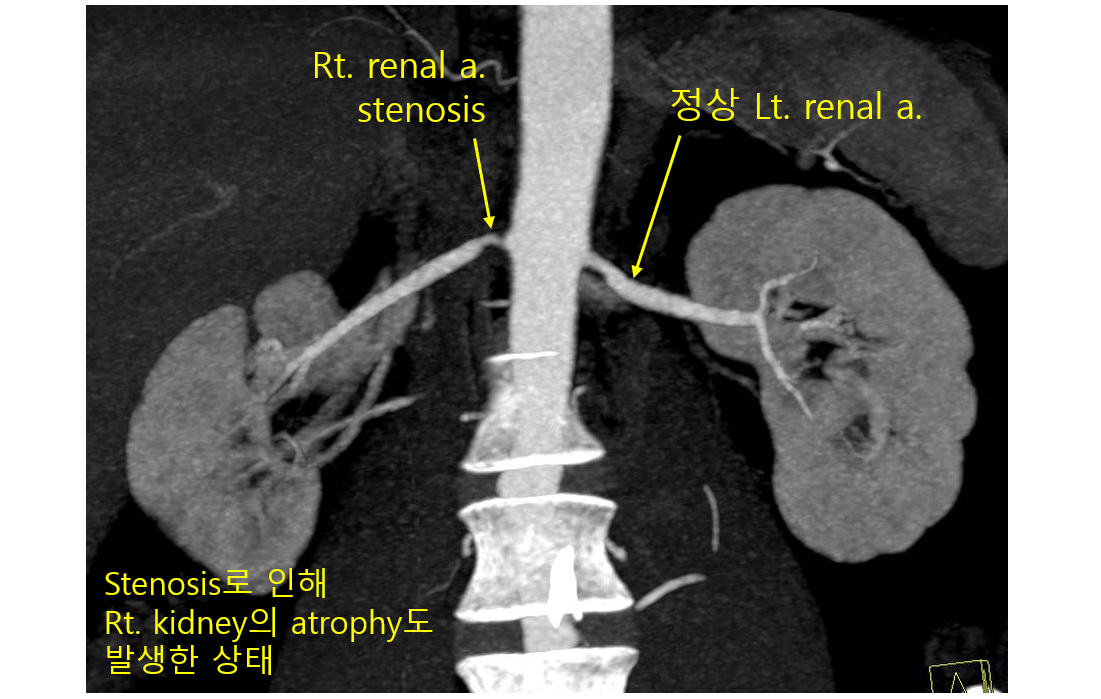

4) 진단: Doppler US, CT/MR angiography가 1st line

(1) 신장 Doppler US

① 한쪽 신장의 크기 감소

② Renal artery 혈류 속도 > 200~300 cm/s 일 경우 협착 시사

(2) CT 혈관조영술(CT angiography)

① 장점: 혈관의 해부학을 잘 볼 수 있음, US와 달리 operator-dependency가 없음

② 단점: 요오드 조영제 투여가 어려울 경우 불가 (ex. 심한 신기능 저하 등)